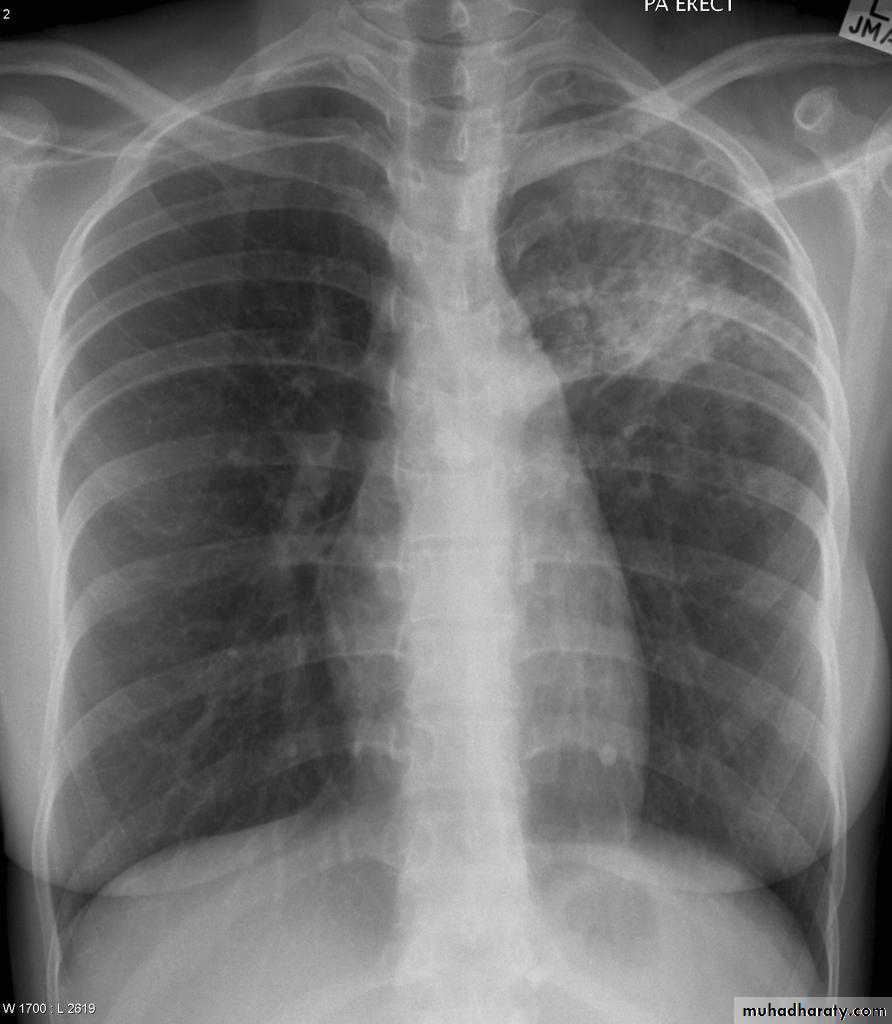

Post primary TB radiographic appearance

Post-primary pulmonary tuberculosis, also known as reactivation tuberculosis or secondary tuberculosis occurs years later, frequently in the setting of a decreased immune status. In the majority of cases, post-primary TB within the lungs develops in either :

* posterior segments of the upper lobes

*superior segments of the lower lobes

Typical appearance of post-primary TB

1.patchy consolidation or poorly defined linear and nodular opacities in both apices , upper zone in one lung , & lower zone in other lung ( ulternating lesion ) .2. Post-primary infections are far more likely to cavitate with multiple abscess formation & air fluid level more develop in the posterior segments of the upper lobes.